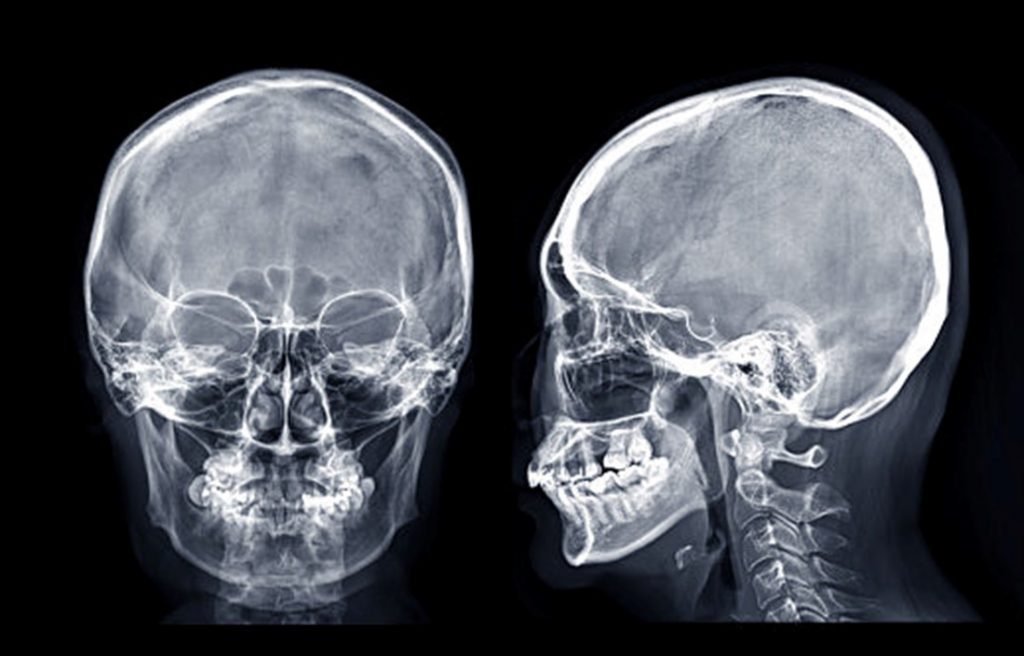

Estudios radiológicos con tecnología digital y mínima exposición a radiación.

Servicio de Rayos X

Contamos con un equipo de profesionales con amplia experiencia en áreas de Radiología

Convencional, Radiología de Emergencia para Traumatología, Procedimientos Especiales con

medios de contraste y Radiología Pediátrica.